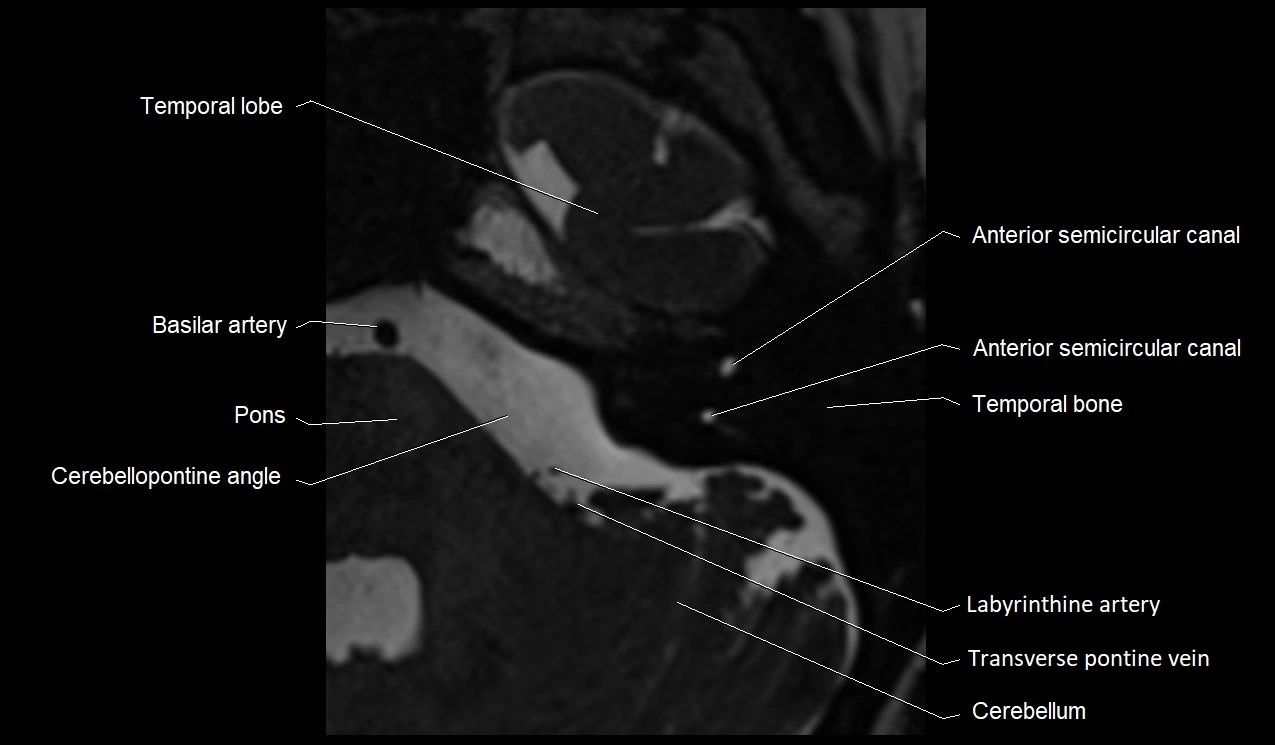

MRI images

image